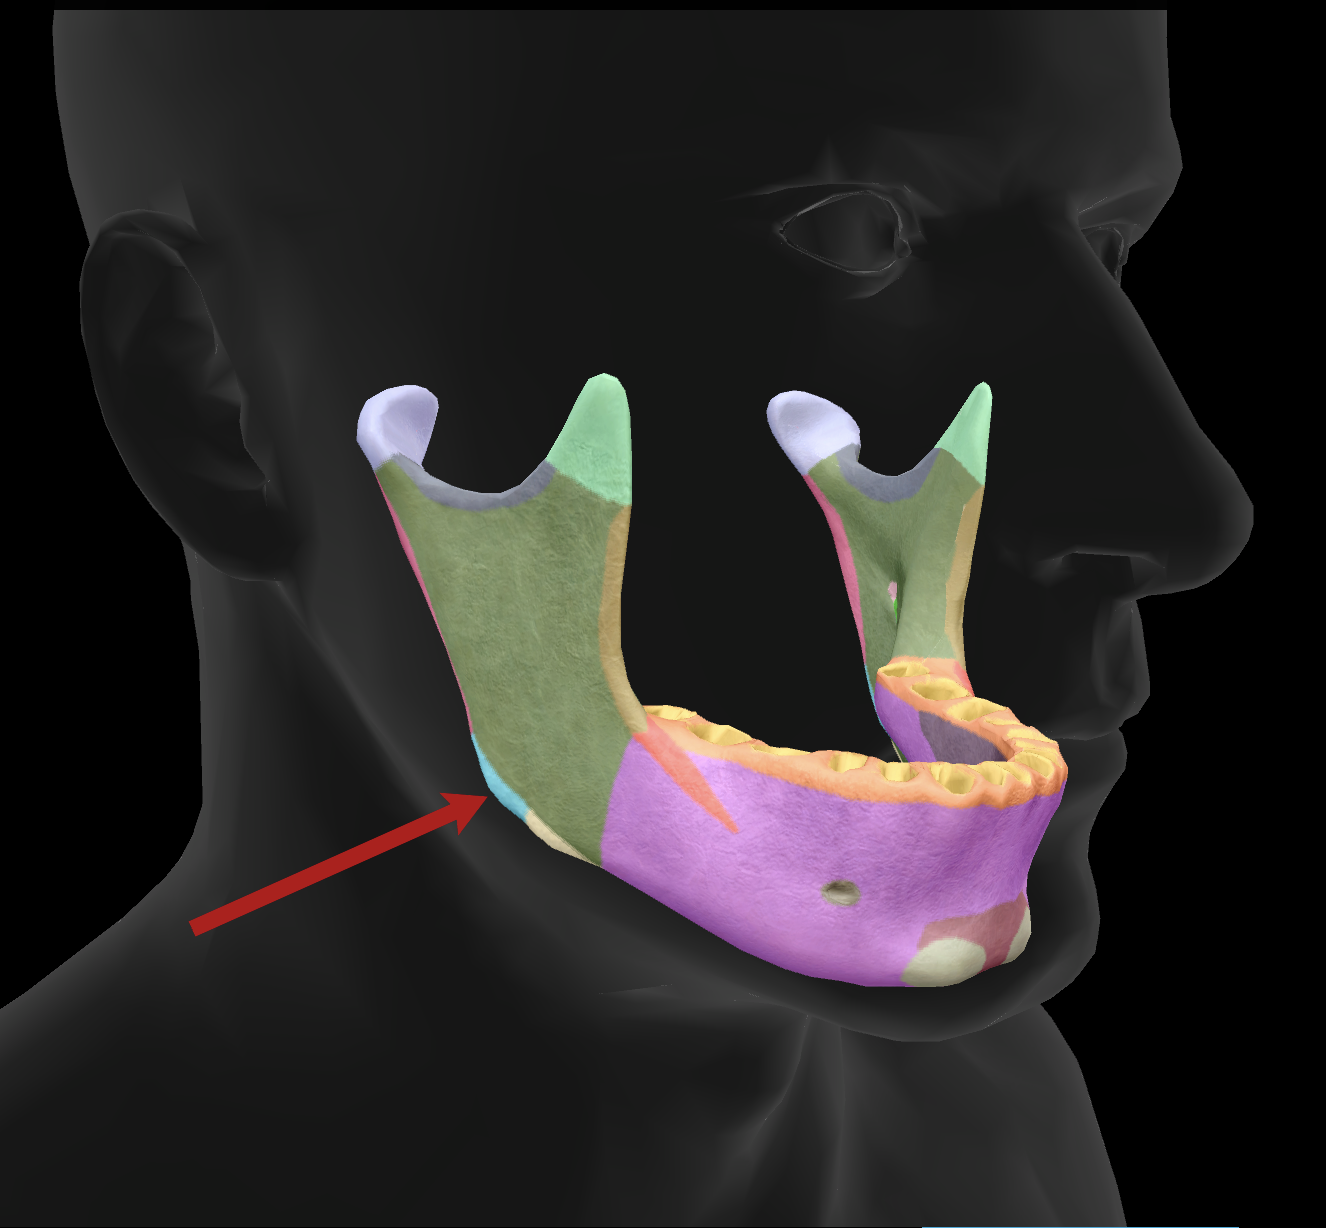

What bone is this?

mandible

What is the name of this feature?

mental foramen

What is the name of this feature?

mandibular condyles

What is the name of this feature?

ramus

What is the name of this feature?

alveolar process

What is the name of this feature?

mandibular notch

What is the name of this feature?

angle

What is the name of this feature?

body

What is the name of this feature?

coronoid process

What is the name of this feature?

mental protuberance